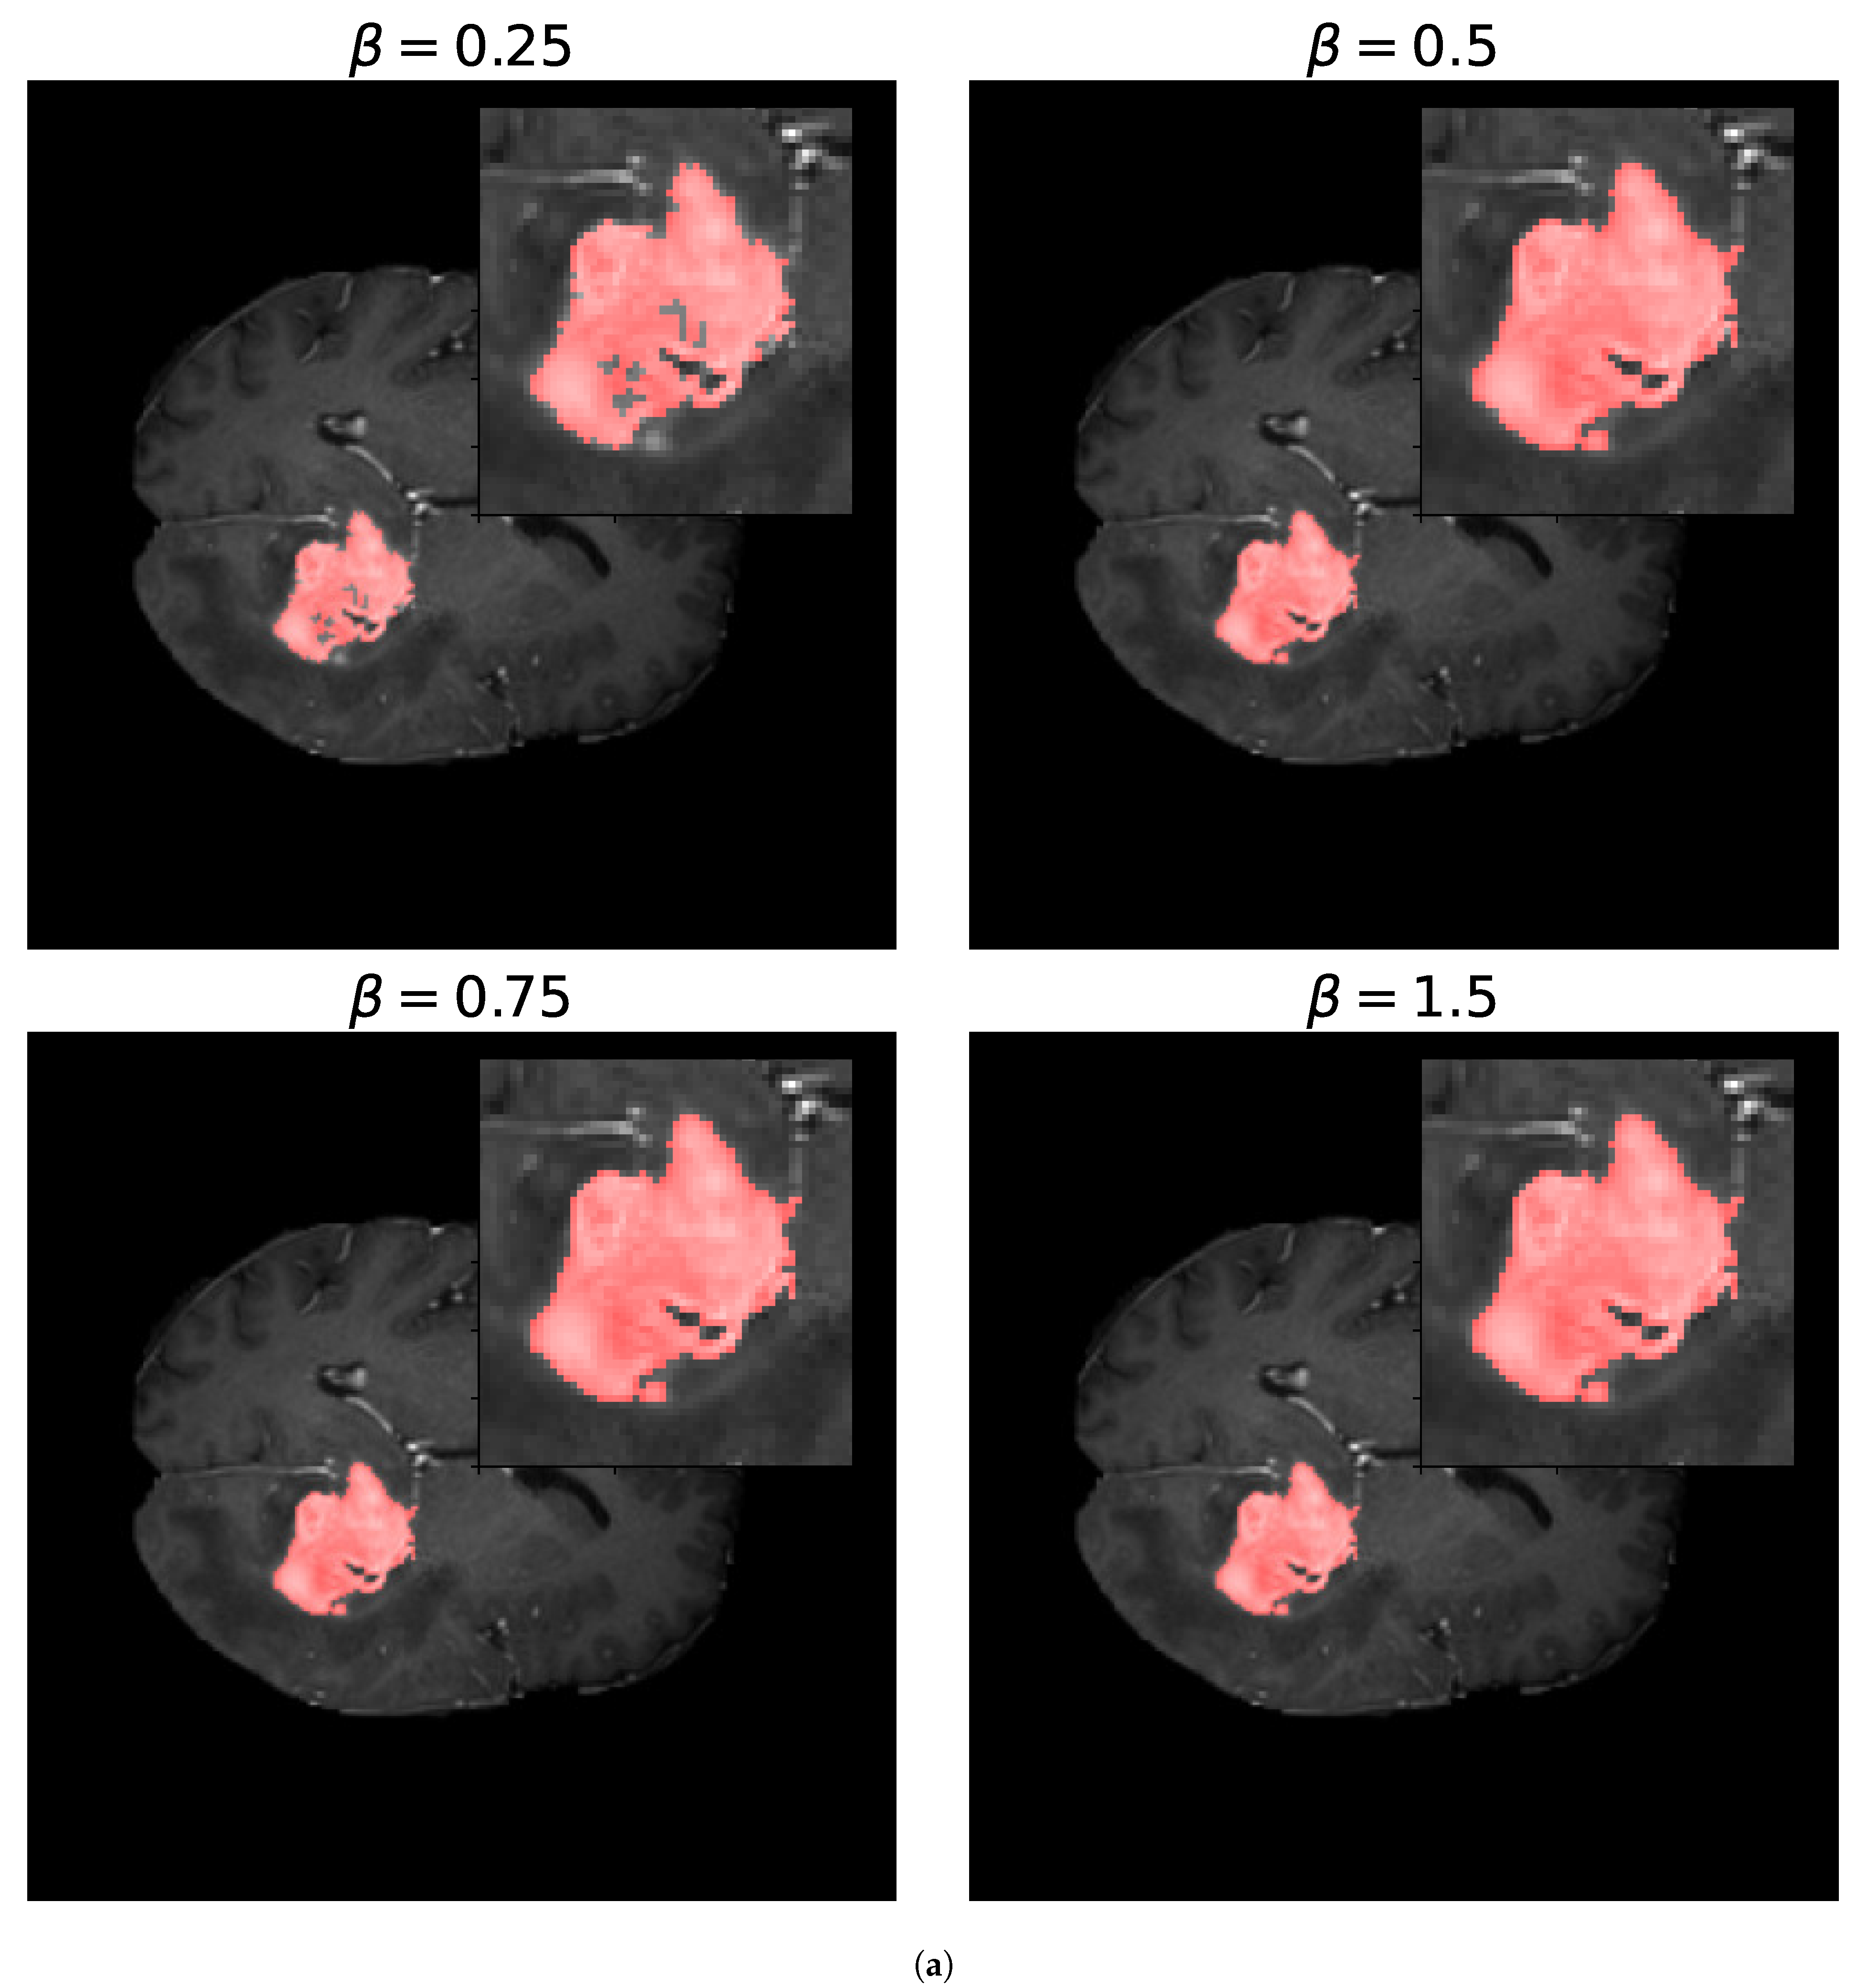

4.3. Optimization Metrics for Biomedical Image Segmentation